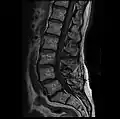

MRI lumbar spine pre-hemilaminectomy (sagittal T2 FRFSE)

-

MRI lumbar spine pre-hemilaminectomy (sagittal T1 FSE)